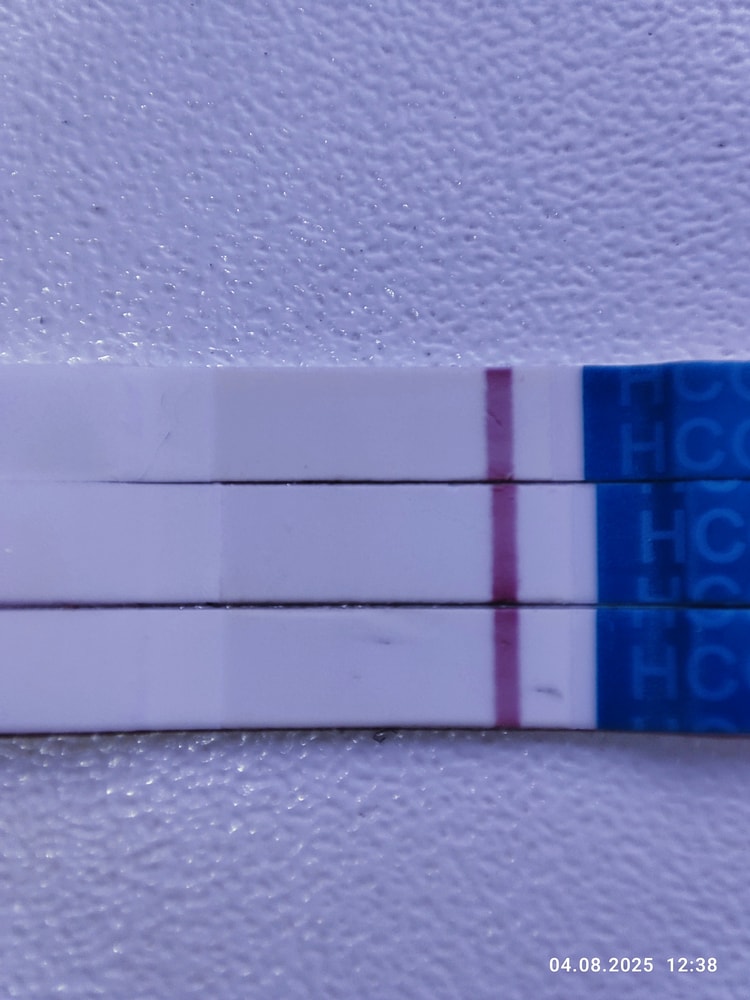

Первые два мама чек

Третий эвик

Мне кажется у эвика что-то есть, но надо повторить однозначтно

Мария Кот, я тоже на эвике вижу, но надо смотреть дальше

Я никогда ничего не вижу на затемненных тестах. Тенюхи видно и так, если они есть.